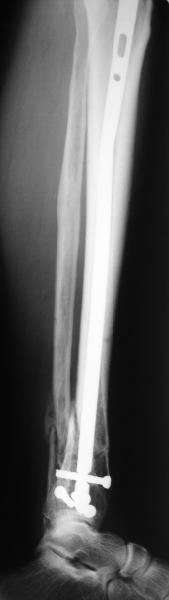

There are some more tricks which allow not to plate the fibula and provide good alignment and stability. A small wire distractor can provide alignment and restore length of both tibia and

fibula. Angular stability of the tibia is provided by insertion of more than two conventional medial-lateral locking screws. To maintain the position of the fibula perQ insertion of a single position screw often could be enough. I bet the articles didn't analyze the options.

A typical case is attached, also an image with intra-op reduction obtained by a small wire distractor, in the moment of insertion a Poller wire in AP direction. Fixation by a SIGN nail. Despite the fibula was not fixed healing was obtained with the unchanged alignment.

[ Ответить ]